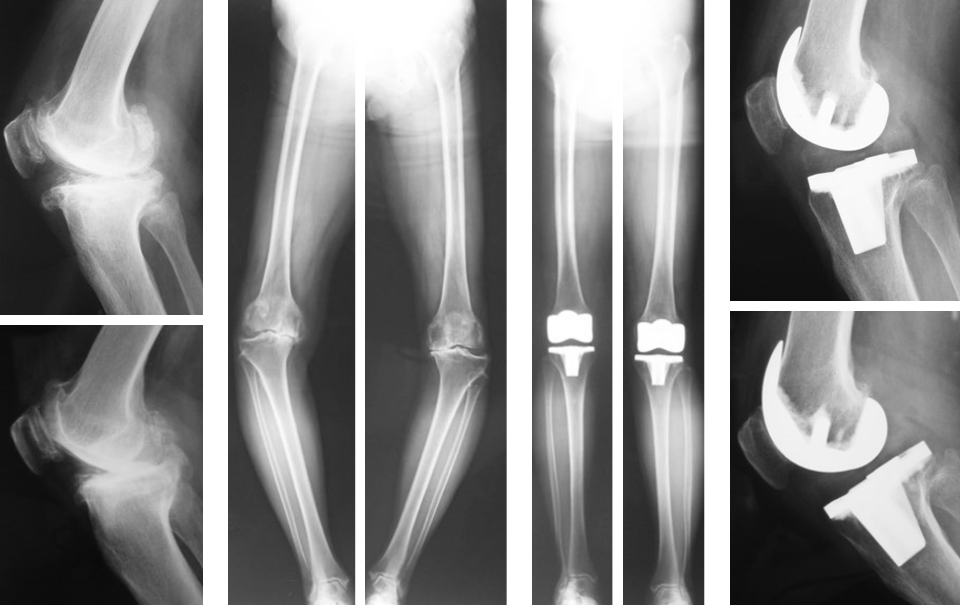

人工膝関節全置換術(TKA)・人工膝関節内側置換術(unicompartmental knee arthroplasty: UKA)

近年、TKAは手術支援ロボットを用いて施行されるようになってきました。当科では2020年9月にZIMMER BIOMET社製のROSA(robotic surgical assistant)

Kneeシステムを全国に先駆け導入しました(図1)。ROSAの特長は術者がプランニングした骨切り位置まで、カットブロックをつけたロボットアームが正確に誘導されることです。またパネルには設置角度、骨切り量、バランス値が0.5㎜、0.5°の単位で可視化され、術者は常にこれらを確認して修正を加えることができます。よって良好な手術手技が期待できます。当科ではこれまでにROSAを使用して210件のTKAを行い、優れた効果を実感しています(2022年5月)。

TKAはおもにOA(図2,3)やRA(図4)、UKAは骨壊死(図5)やOAの内側罹患例に行います。左右罹患例には両膝同日手術も施行しています(図3)。手術の目的は除痛、膝関節機能の回復によるADL、QOLの改善です。

人工膝関節は多機種ありますが、当科では自家組織(骨や靭帯)温存に配慮して、主に前十字靭帯のみ切除するCR型を選択し、膝蓋骨は非置換、セメントレス用コンポーネントを用いています(図2)。後療法は両側例でも翌日から離床と荷重を許可し、入院加療は約2週間です。

図3 両側OAに対する両側同日TKA

図4 RAに対するTKA